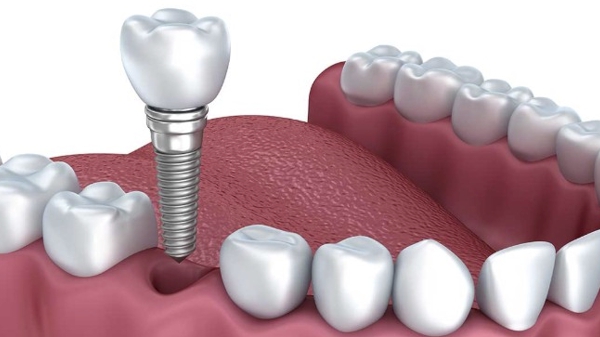

IMPLANTODONTIA

É a especialidade que tem como objetivo implantação na mandíbula e na maxila de uma nova geração de implantes, que são parafusos ...

IMPLANTODONTIA

É a especialidade que tem como objetivo a implantação na mandíbula e na maxila de uma nova geração de implantes, que são parafusos de titânio, colocados em áreas edêntulas que funcionam como raízes artificiais e apresentam capacidade de exercer as funções mastigatórias de maneira semelhante aos dentes naturais.

O titânio é o metal utilizado na fabricação dos implantes orais, além de altamente resistente, também é "biocompatível", ou seja, pode permanecer no organismo humano sem rejeição ou danos ao tecido ósseo.

Dentro das especialidades odontológicas, é a área que apresentou maior evolução nos últimos anos, tornando-se um recurso importante nas reabilitações orais. Pesquisas indicam que mais de 500 mil implantes dentários são realizados no mundo anualmente, e que as taxas de sucesso são de aproximadamente 95 a 98%.